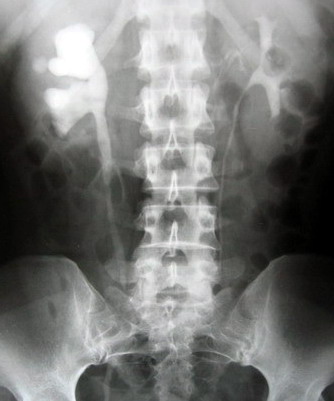

泌尿系結(jié)石是最常見(jiàn)的泌尿外科疾病之一,包括腎結(jié)石、輸尿管結(jié)石、膀胱結(jié)石和尿道結(jié)石。約5%-10%的人在一生中至少要發(fā)生1次尿路結(jié)石。尿結(jié)石的主要表現(xiàn)為:腰腹部疼痛、血尿、惡心、嘔吐及尿頻、尿不凈等膀胱刺激癥狀。因發(fā)病突然,疼痛劇烈,常常難以忍受。

該手術(shù)對(duì)于輸尿管中下段結(jié)石可在發(fā)病后快速進(jìn)行腔內(nèi)碎石,不用開(kāi)刀,經(jīng)尿道碎石,無(wú)需特殊術(shù)前準(zhǔn)備,患者發(fā)病后可立即進(jìn)行手術(shù),直接將結(jié)石擊碎取出,甚至術(shù)后無(wú)需留置導(dǎo)尿管和輸尿管支架管,這樣避免了腰椎穿刺引起的腰痛及頭痛等腰麻的并發(fā)癥。術(shù)前、術(shù)后都無(wú)需禁食,對(duì)合并糖尿病的患者更好管理。術(shù)后無(wú)管化也避免了插管給病人帶來(lái)的疼痛不適。住院時(shí)間明顯縮短,一般術(shù)后48小時(shí)可出院,整個(gè)住院費(fèi)用減少1/3—1/2。手術(shù)效果可謂立竿見(jiàn)影,立即解除痛苦,該技術(shù)處于全國(guó)領(lǐng)先水平。針對(duì)輸尿管中下段結(jié)石,可作為一種常規(guī)手術(shù)方式進(jìn)行全面推廣。同時(shí),濰坊市市立醫(yī)院泌尿外科目前還擁有全國(guó)最先進(jìn)的體外沖擊波碎石機(jī),德國(guó)進(jìn)口輸尿管鏡、經(jīng)皮腎鏡,瑞士進(jìn)口EMS氣壓彈道碎石機(jī)。歡迎廣大病友咨詢(xún)。